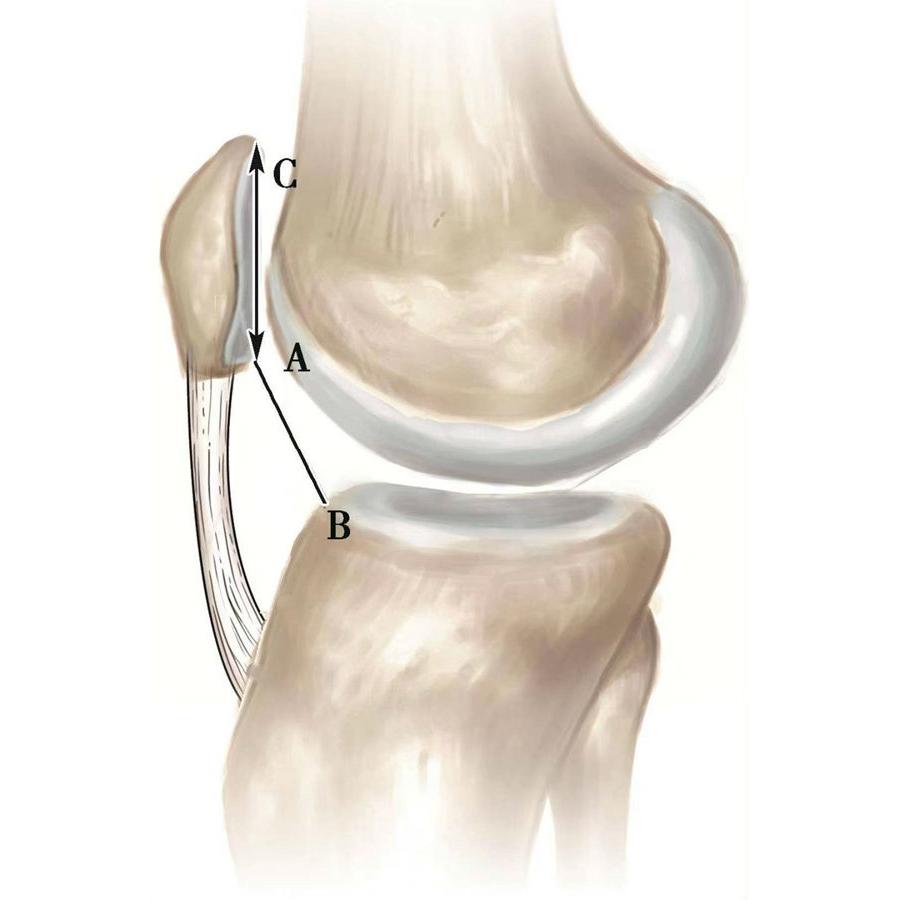

如图示:AB为髌骨关节面最低点到胫骨平台轮廓前上角最短的距离,AC是髌骨关节面的长度。Caton指数=AB/AC(图1)。

图1

图2 Caton指数=AB/AC=1.10,为正常髌骨高度

临床工作中常常使用其来估计胫骨结节移位的效果。正常人的Caton指数=1,正常范围0.8~1.2(图2)。需要注意的是:术前规划胫骨结节需要移位的理论距离为AB-AC,这就是需要将胫骨结节向远端移位的最大距离。但在术中胫骨结节转移的距离往往要小于这个距离,避免因过度移位造成医源性的低位髌骨。